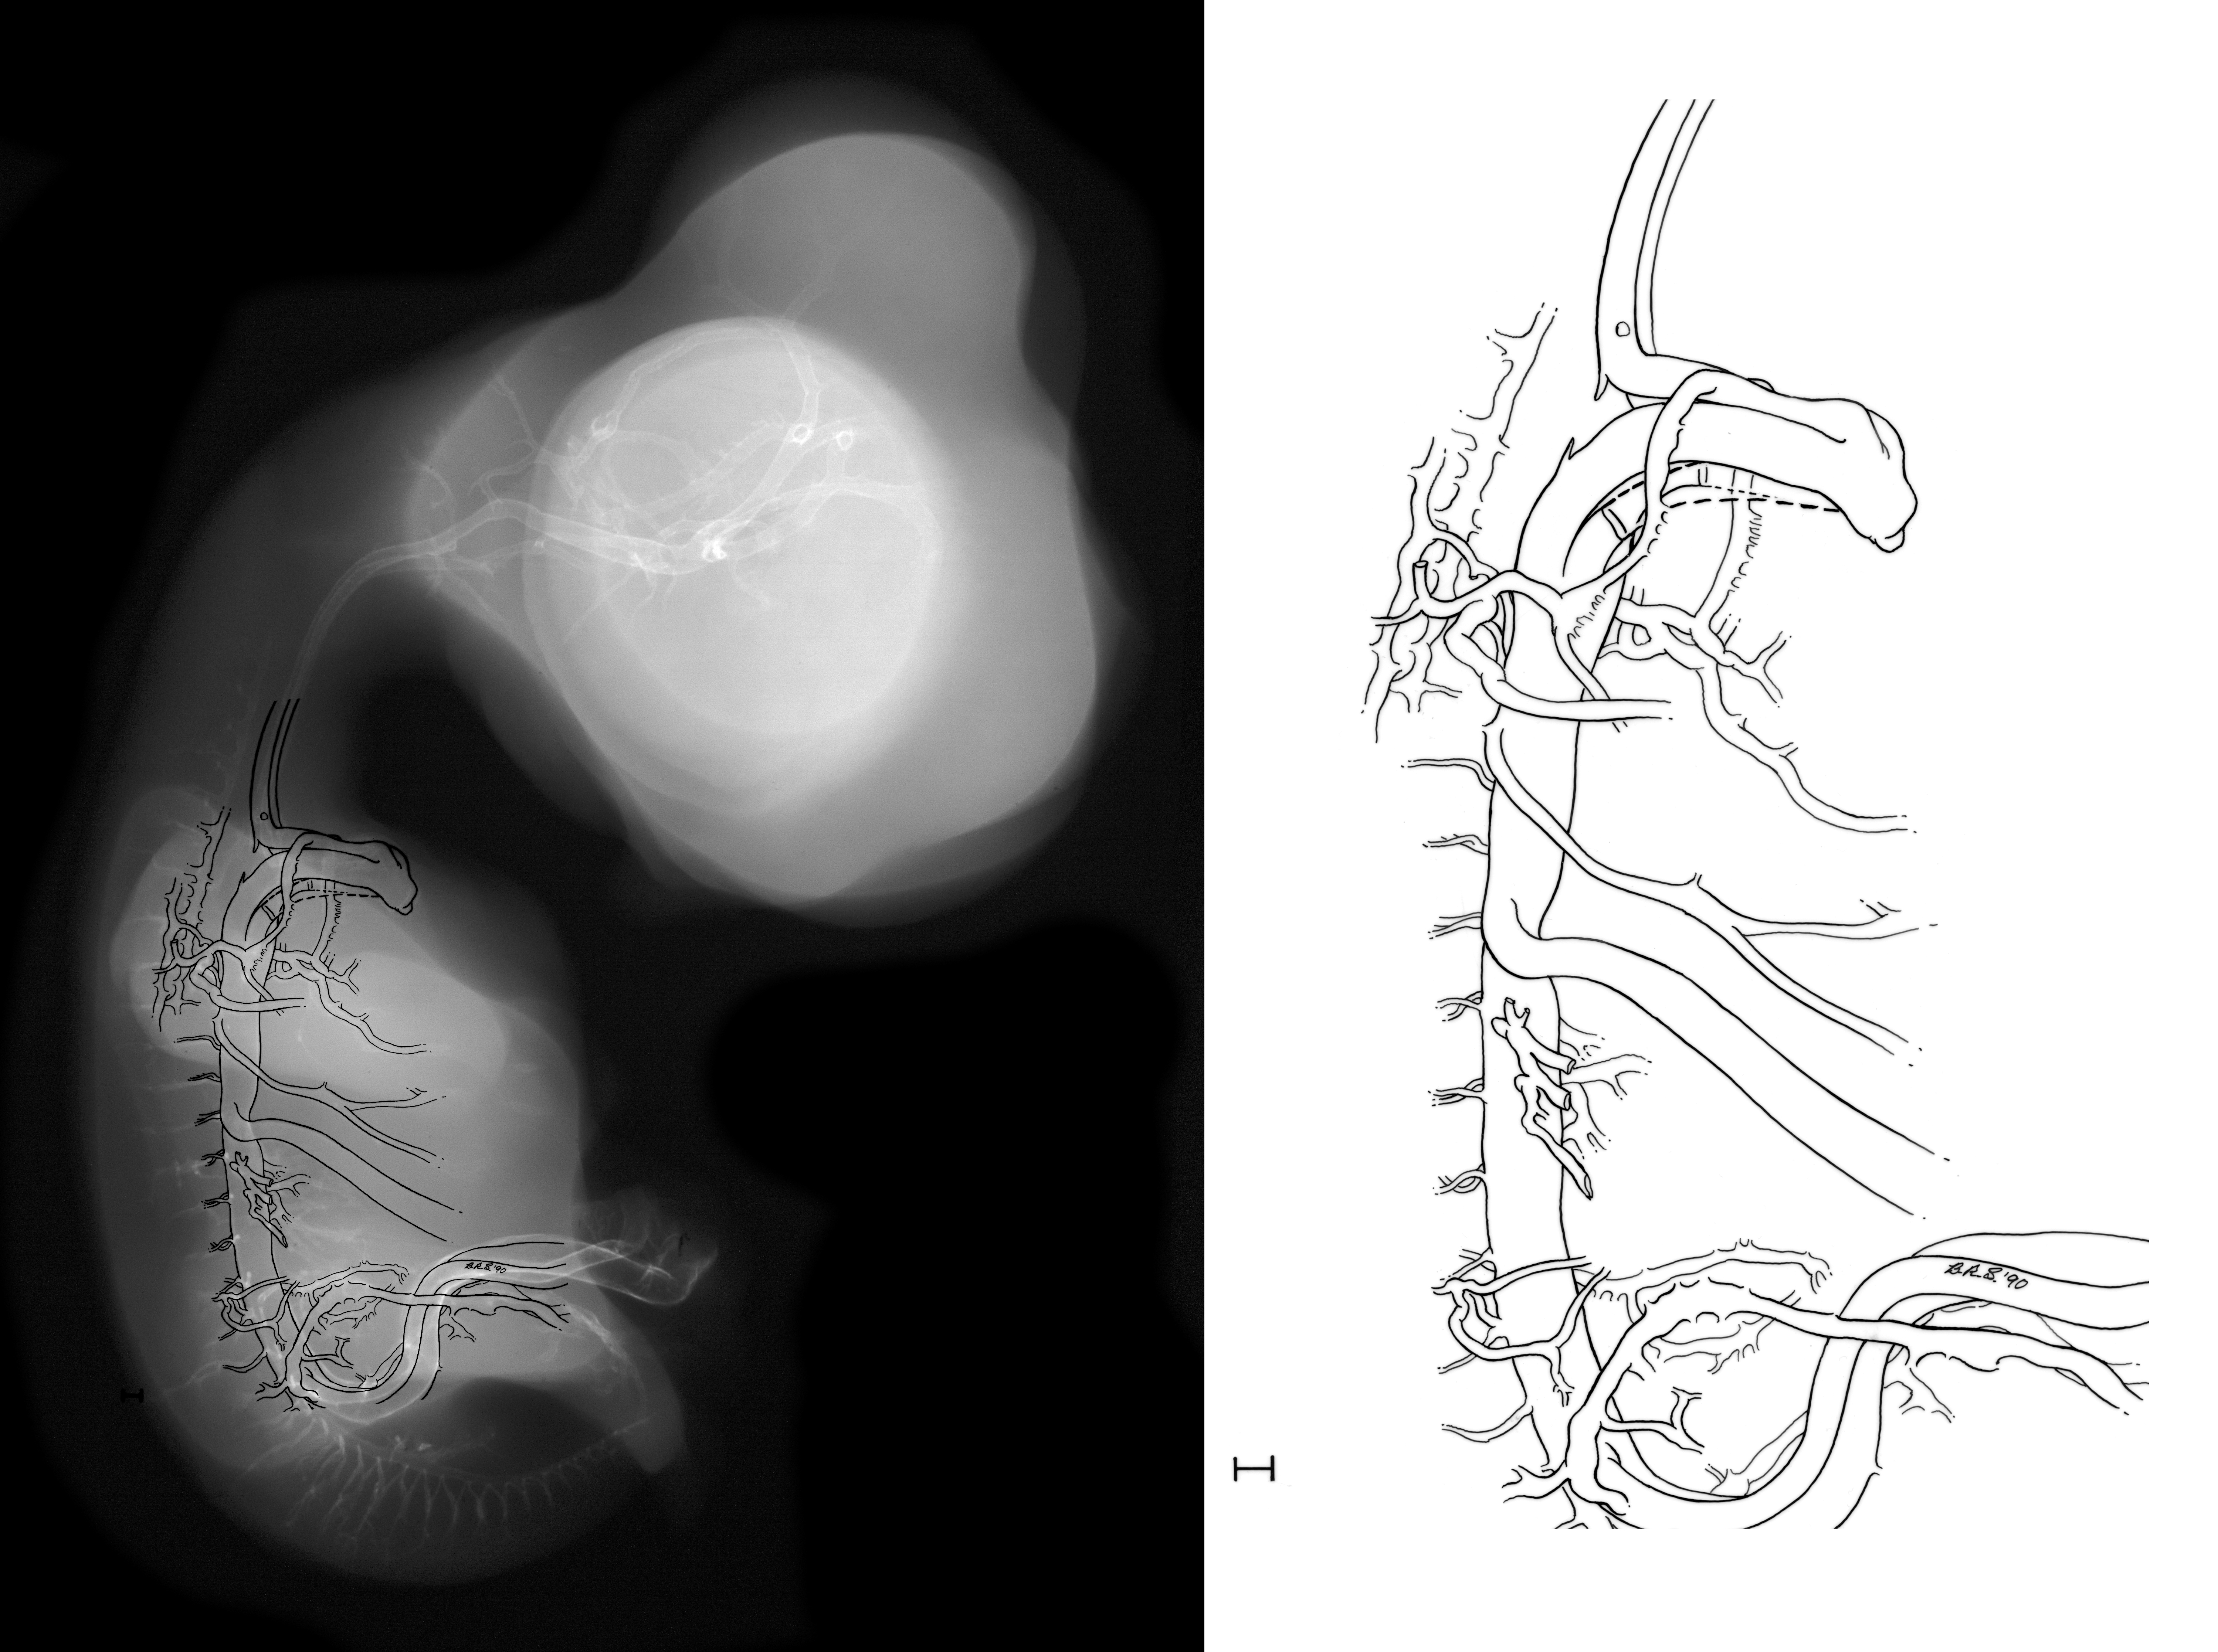

Chick Embryo Microangiography

Hamburger-Hamilton (HH) Stage 30 (approx. 6.5 days)

X-Ray Micrographs

Stereo X-Ray Micrographs

Drawing